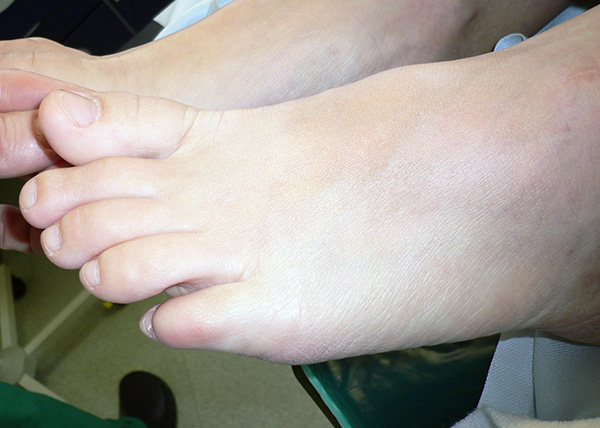

Zentraler Vorfuß

Eine topographische Gliederung des Vorfußes ist in den ersten Strahl, den 5 Strahl und den zentralen Vorfuß möglich. Probleme des zentralen Vorfußes können weiter unterteilt werden in Zehenfehlstellung und Beschwerden im Sinne einer Metatarsalgie. Unter Metatarsalgie versteht man Schmerzen unter dem zentralen Vorfuß, insbesondere im Bereich der Mittelfußköpfchen 2-4 1213. Die Metatarsalgie ist somit durch die Kombination aus Symptom (Schmerz) und Lokalisation definiert. Unterschiedliche Krankheitsentitäten können zum klinischen Bild einer Metatarsalgie führen.

Die klinische Untersuchung des zentralen Vorfußes beginnt mit einer Untersuchung der Kleinzehen beginnen. Dabei ist die Zehe immer in Zusammenhang mit dem Zehengrundgelenk zu beurteilen. Dabei muss jedes Gelenk der Zehe einzeln untersucht werden. Darüber hinaus ist die Funktion der Zehe einzuschätzen. Kommt es zu einem Bodenkontakt der Zehenkuppe bei Aktivierung der Beugesehnen?